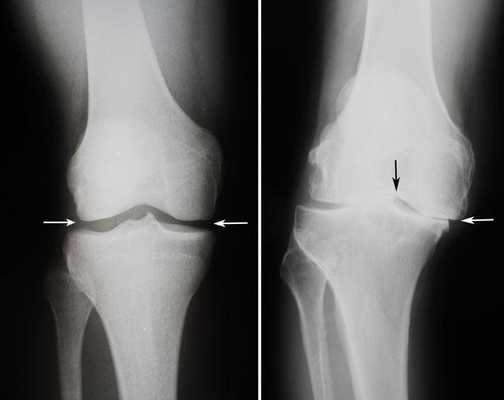

Длительное время ТЭКС (тотальное протезирование коленного сустава) признавался ведущим методом при лечении остеоартроза. Какие же преимущества имеет одномыщелковое эндопротезирование:

- Гораздо меньший объем хирургического вмешательства;

- Быстрый восстановительный период (уже через несколько месяцев пациент может возвращаться к своим повседневным физическим нагрузкам);

- Менее выражен болевой синдром (как в покое, так и при интенсивной физической нагрузке);

- После частичного эндопротезирования люди вдвое реже жалуются на трудности при использовании автомобиля, чем после тотального;

- Вдвое меньше случаев ограничения сгибания в коленном суставе и контрактур;

- Гораздо чаще людям с частичным эндопротезом доступно положение сидя на корточках, посадка и выход из автотранспорта, наклон и подъем предметов с пола, бег.

Целый ряд неоспоримых и важных преимуществ однополюсного протезирования. Большинство зарубежных коллег подчеркивают у себя схожесть приведенных результатов.

Сравнение двух типов операций.

Две техники операции у одного пациента.